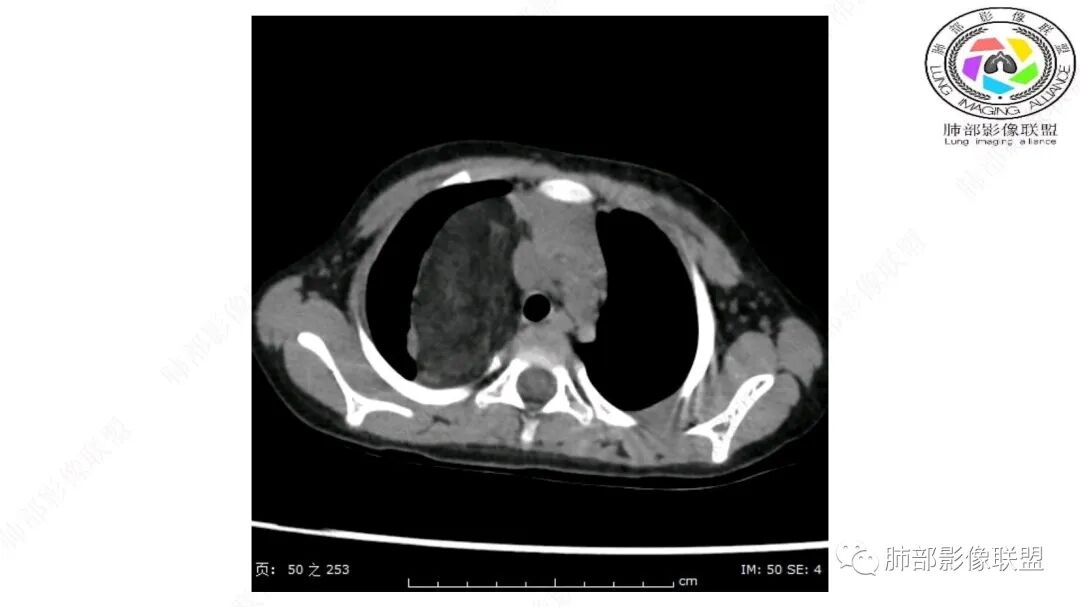

定位:肺内?尖段气管未见明显显示,腔静脉受压向右推移?病灶内可见前段动脉穿行,脂肪密度为主。

肿块起源于右上气管分叉处?强化动脉血管最后汇入右肺动脉上干。

右侧纵隔奇静脉水平起源?压迫上肺,包绕动脉?

跨肺门,包绕肺血管分支,邻近肺组织受压肺不张。

可以看到造影剂进入的丛状结构

密度不均,非纯脂肪成分。斑片状密度略高区域有轻度填充式强化。

第一个问题:定位:肺内?纵隔?

病灶属于交界区,主体位于肺内,占位效应明显,前方突入胸壁,胸腺受压变形,胸膜显示欠清楚;病灶包绕上叶肺动脉;似乎有体动脉供血。符合肺内的点:包绕上叶肺动脉分支;符合纵隔的点:前方似乎突入胸壁,与胸腺关系比较密切,但是与上腔静脉的关系提示病灶不支持纵隔来源,前纵隔的常规会将上腔静脉受压后移、外移,这是不符合的。

从这个角度符合肺内的,有一点不太踏实的是:似乎突入前胸壁。